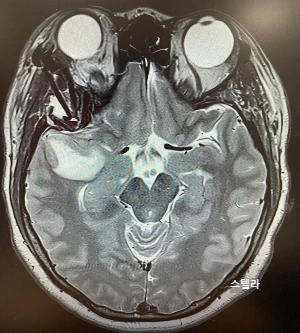

수술 전

수술 직후

교수님은 수술 전 후 MRI 사진을 비교해 주셨다.

사진을 보고 있자니 나도 모르게 눈물이 났다.